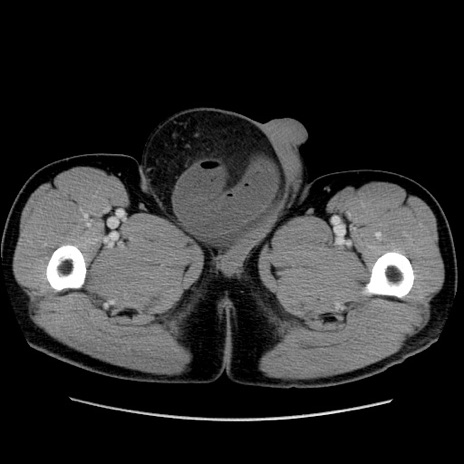

症例34(横断像)

【症例】60歳代 男性

【主訴】右鼠径部膨隆

【現病歴】1年程前より右鼠径部膨隆あり。自己にて還納可能だったため放置していた。3時間前より右鼠径部の脱出を認め、還納困難となり受診。

【既往歴】高血圧

【身体所見】右鼠径部に小児頭大の膨隆あり。弾性硬であり、用手還納は困難。左鼠径部にも膨隆を認める。脱出はなし。